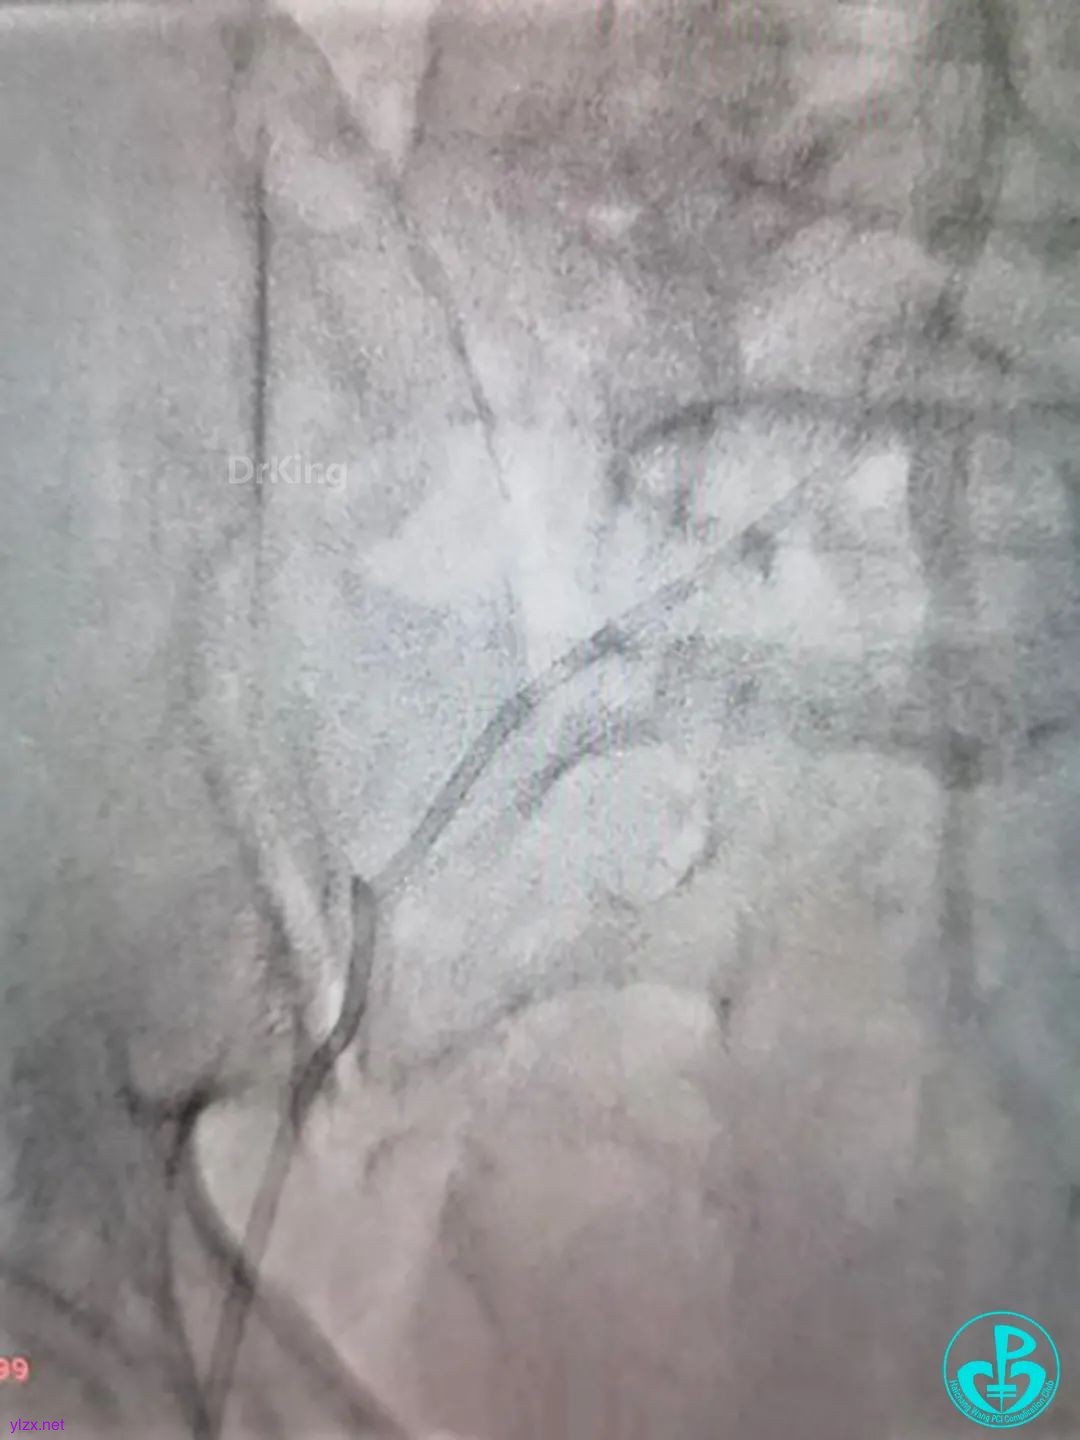

走左边,终于到位,造影。

左边EBU。

简单处理。

血运重建完成,胸痛缓解。生命体征平稳!